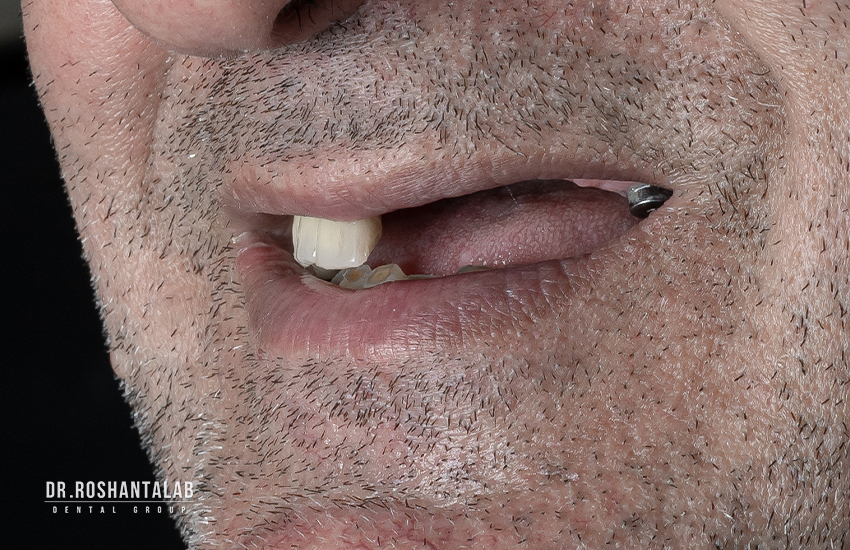

تاثیر روی زیبایی شناسی چهره

دندان های شما روی ساختار و شکل چهره شما تاثیر می گذارند. از دست دادن دندان روی زیبایی شناسی چهره تاثیر بسیار زیادی دارد. استخوان فک تحلیل رفته در اثر از دست رفتن دندان، چهره شما را بسیار پیرتر نشان می دهد. اگر به چهره افرادی با دست دندان متحرک که دندان خود را بیرون آورده اند دقت کنید، متوجه تاثیر نداشتن دندان بر ظاهر فرد می شوید.

دلایل زیادی میتواند موجب شود که شخص در طول دوره زندگی اش دندان یا دندان های خود را از دست بدهد. تروما دندان، ضربه خوردن دندان و حتی کشیدن دندان از جمله این دلایل میتواند باشد. مشکلات در تکلم و تلفظ کلمات، مشکل در جویدن غذا و مشکلات گوارشی، ناهنجاری در اکلوژن دندانها، تحلیل استخوان فک و جابجایی دندان ها بخش کوچکی از مشکلات و عوارض نداشتن دندان است که فرد با آن ها روبرو خواهد شد. به علاوه این موضوع اگر برای دندانهای جلو پیش آید تاثیر زیادی در چهره فرد خواهد داشت. این مورد یکی از مهمترین موارد عوارض بی دندانی است که تاثیر زیادی در اعتماد به نفس فرد دارد. اگر جای خالی دندان افتاده شده جایگزین نشود، بر لبخند فرد هم تاثیر میگذارد و مشکلاتی را هنگام لبخندزدن برای او به همراه دارد.